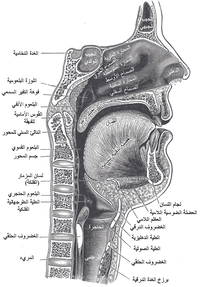

جوف الأنف أو الحفرة الأنفية إنگليزية: Nasal Cavity هو الجزء العميق من الأنف والممتد من المنخرين في الأمام وحتى المنعرين في الخلف[1][2]، أي حتى البلعوم في الخلف.[3] يقسم جوف الأنف إلى قسمين أيمن وأيسر بواسطة بنية عظمية غضروفية تدعى حاجز الأنف أو الوتيرة.[1]

الحدود التشريحية

الجدار العلوي

يسمى الجدار العلوي لجوف الأنف بسقف الأنف، يساهم في تشكيله من الأمام للخلف كل من غضاريف الأنف والعظم الأنفي والجبهي وجسم العظم الوتدي والصفيحة المصفوية للعظم الغربالي. يمر عبر ثقوب الصفيحة المصفوية ألياف العصب الشمي التي تنقل الإشارات المسؤولة عن حاسة الشم.[1][2]

الجدار السفلي

يسمى أرضية الأنف أو قاع الأنف ويتمثل بالحنك الصلب. يفصل الحنك الصلب جوف الأنف عن جوف الفم[1][2] وتتشكل ثلاثة أرباعه الأمامية من الناتئين الحنكيين للفكين العلويين في حين يتشكل ربعه الخلفي من الصفيحتين الأفقيتين للعظمين الحنكيين. أرضية الأنف مقعرة قليلاً بالعرض وأفقية تقريباً بالمستوى الأمامي الخلفي. يرى أحيانا في الجزء الأمامي الأنسي من الأرضية انخفاض صغير يدعى الردب الأنفي الحنكي.[6]

الجدار الوحشي

يعتبر الجدار الوحشي أكثر جدران جوف الأنف تعقيداً؛ إذ يساهم في تركيبه كل من العظم الأنفي والغربالي والدمعي والفكي العلوي والصفيحة العمودية للعظم الحنكي والصفيحة الجناحية الأنسية للعظم الوتدي. يتميز الجدار الوحشي ببروز ثلاث تراكيب عظمية تتوضع فوق بعضها تدعى المحارات الأنفية.[1][6] كما يتميز الجدار الوحشي بوجود ارتفاع دائري ينتج عن بروز الخلايا الغربالية المتوسطة نحو الأنسي يدعى الفقاعة الغربالية، وإلى الأسفل والأمام من هذه الفقاعة يوجد ثلم متقوس يدعى الفرجة الهلالية.[6]

الجدار الأنسي

يسمى الجدار الأنسي لجوف الأنف حاجز الأنف. غالبًا ما يكون حاجز الأنف منحرفًا عن الخط الناصف مما يؤدي إلى كبر أحد قسمي جوف الأنف على حساب الآخر.[6] يتركب حاجز الأنف من قسم أمامي غضروفي يشكله أحد غضاريف الأنف، ومن قسم عظمي يشكله العظم الغربالي والميكعة.[1]

التقسيم التشريحي

يقسم جوف الأنف بواسطة حاجز الأنف إلى قسمين أيمن وأيسر، ويقسم كل منهما بواسطة المحارات الأنفية الثلاثة إلى أربع فسحات هي من الأعلى للأسفل:

- الردب الوتدي الغربالي: يقع فوق المحارة الأنفية العلوية وخلفها.

- الصماخ الأنفي العلوي: يقع تحت المحارة العلوية ووحشيها.

- الصماخ الأنفي الأوسط: يقع تحت المحارة الأنفية الوسطى ووحشيها.

- الصماخ الأنفي السفلي: يقع تحت المحارة الأنفية السفلية ووحشيها.[1]

يسمى القسم الأمامي من جوف الأنف والمحاط بغضاريف الأنف بالدهليز.[7]

الاتصالات

يتصل جوف الأنف مع الوسط الخارجي في الأمام عبر المنخر ويتصل مع البلعوم الأنفي في الخلف عبر فتحة بيضية الشكل تدعى المنعر. كما يتصل جوف الأنف مع الجيوب جانب الأنفية عبر فتحات خاصة، ويسمح وجود هذه الفتحات بتفريغ محتويات الجيوب ومنع تراكمها. تفتح القناة الأنفية الدمعية التي تنقل الدمع على الصماخ الأنفي السفلي.[1][6][8] يفتح على جوف الأنف في الجمجمة الجافة (أي بعد إزالة المخطيات) بالإضافة لما سبق كل من الثقبة الوتدية الحنكية والنفق القاطعي والصفيحة المصفوية.[1]

التعصيب

- الحس العام: عن طريق فروع من أول فرعين للعصب مثلث التوائم (العيني والفكي العلوي). فالأجزاء الأمامية لجوف الأنف يتم تعصيبها بواسطة العصب الغربالي الأمامي فرع العصب الأنفي الهدبي (الذي بدوره يتفرع من العصب العيني)، أما الأجزاء الخلفية من جوف الأنف يتم تعصيبها عبر فروع للعقدة الجناحية الحنكية والتي تصلها ألياف من العصب الفكي العلوي.

- حس الشم: عن طريق ألياف العصب الشمي التي تعبر الصفيحة المصفوية.[1]